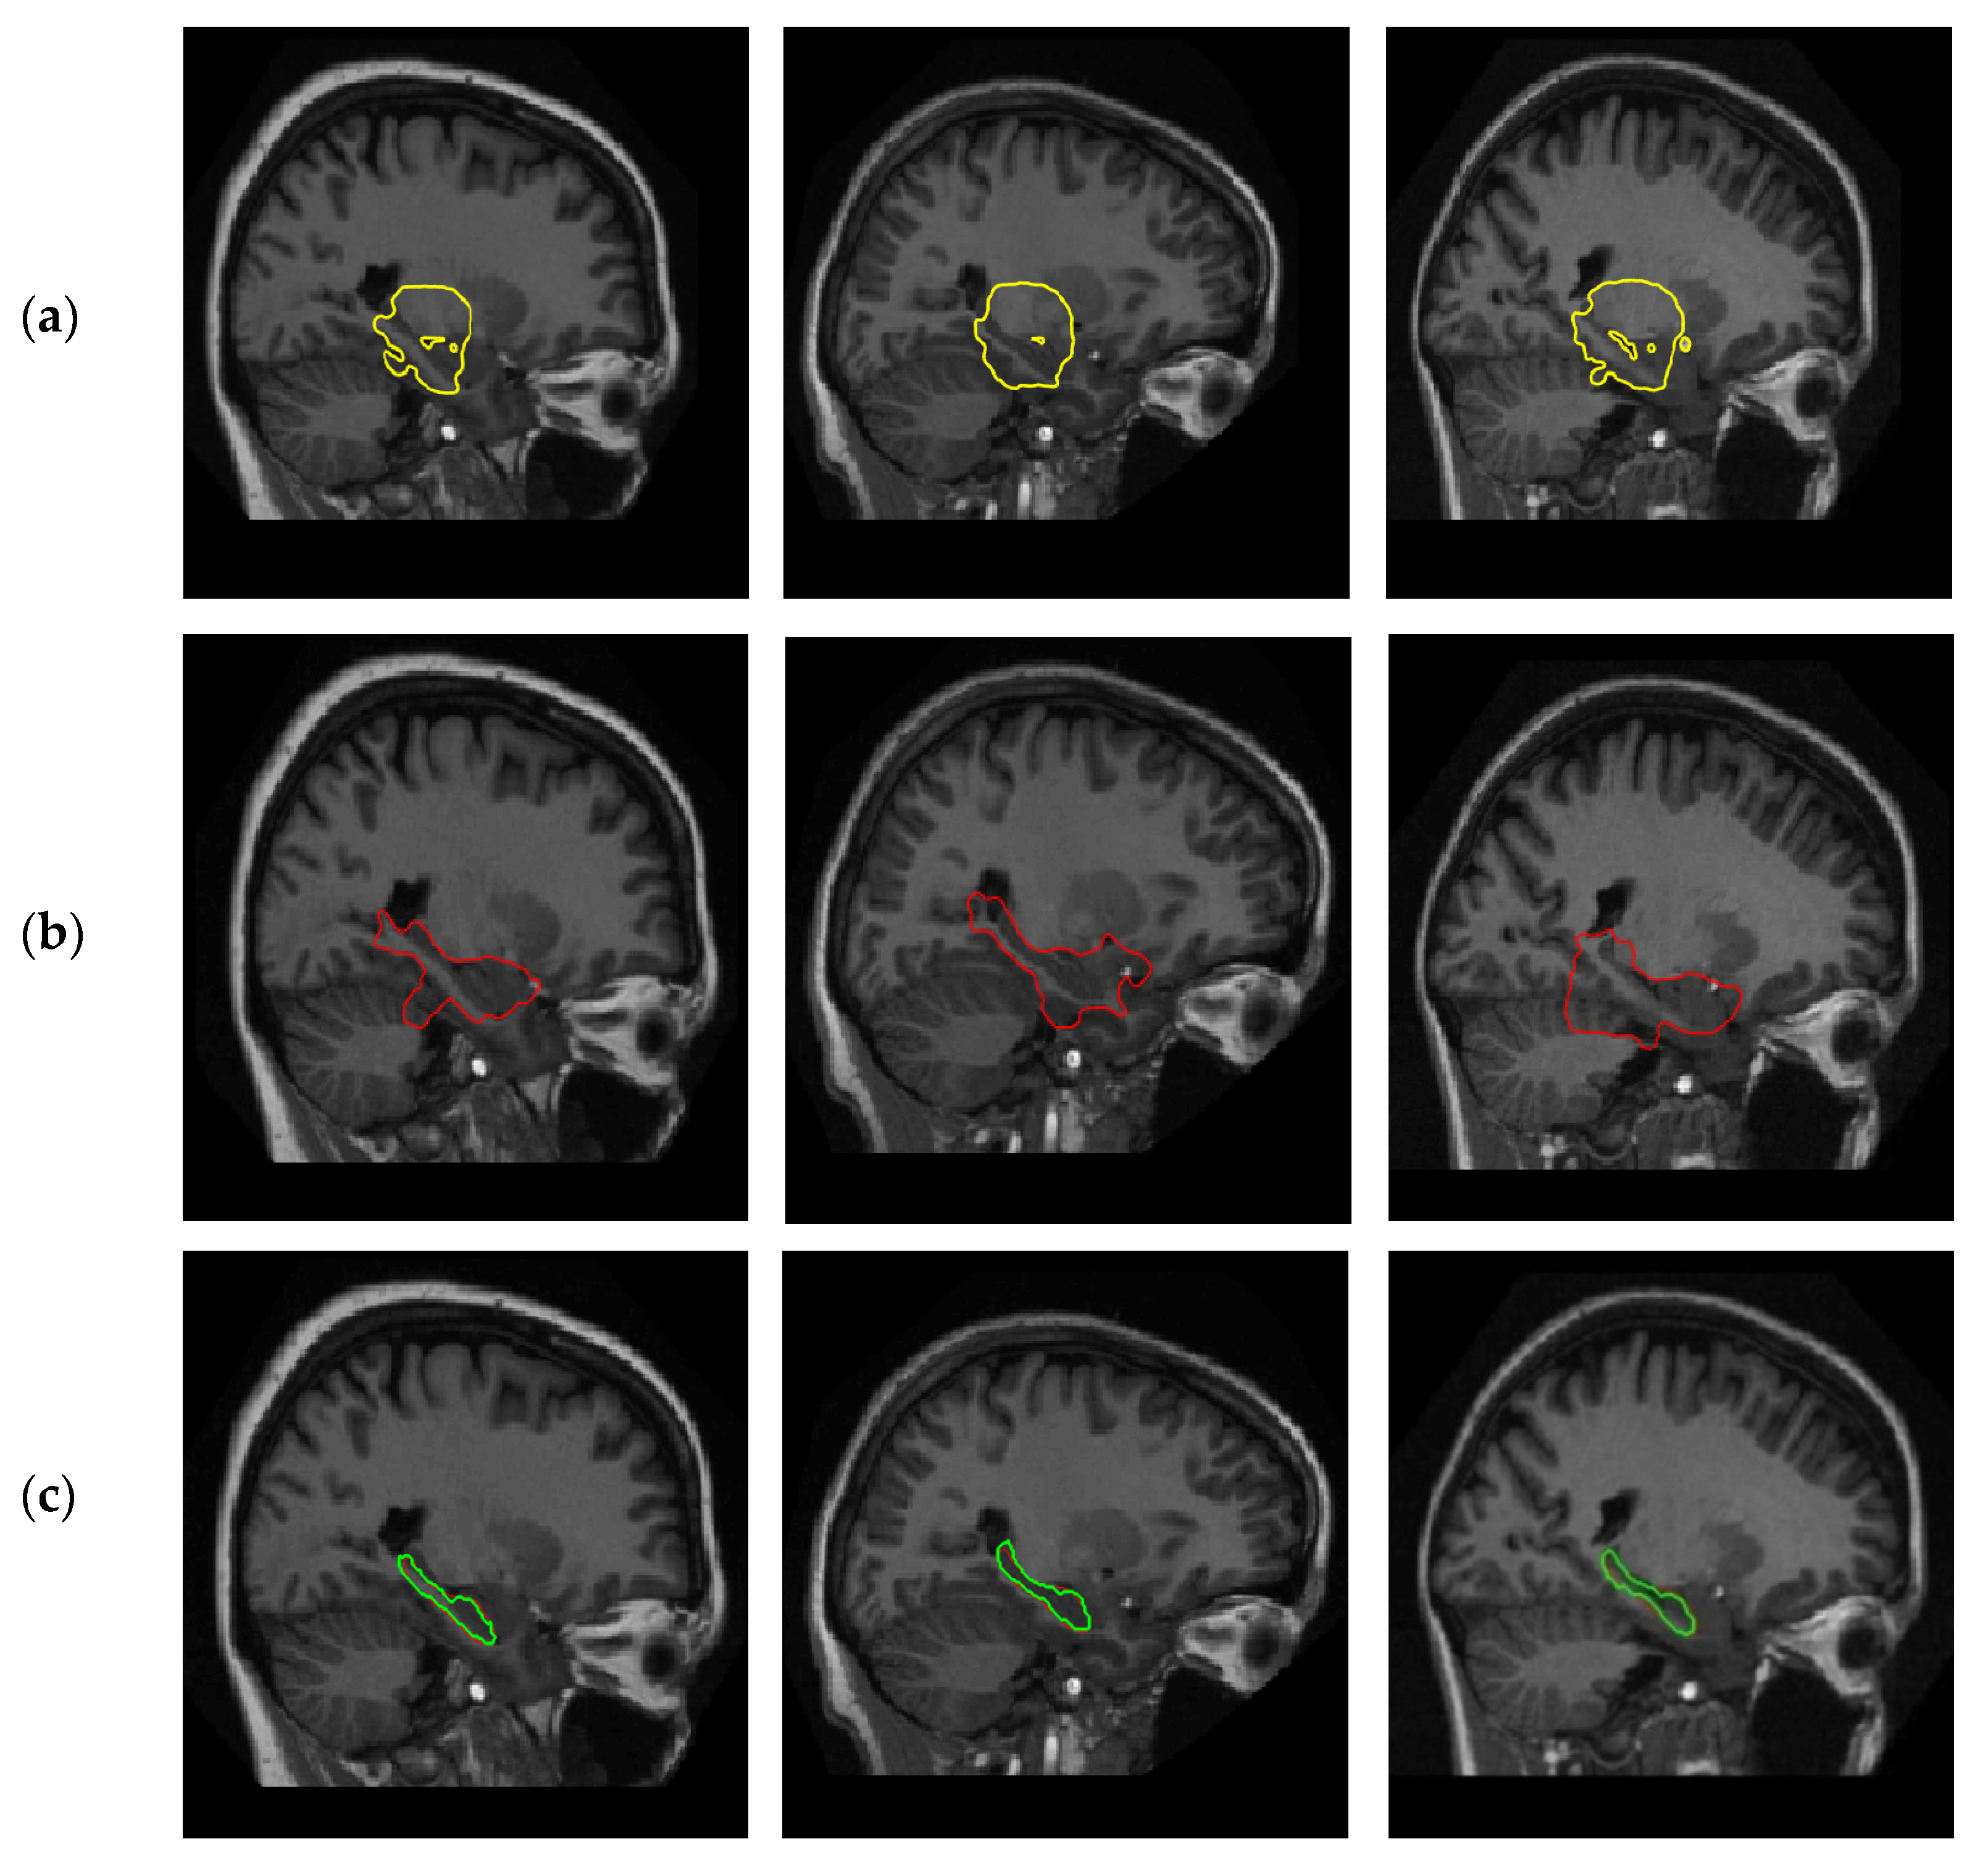

4.1. Positive Effect of Shape Prior

4.2. Sensitivity to Shape and Size Change

4.2.1. Experiments on Synthetic Images

4.2.2. Experiments on Hippocampus Images